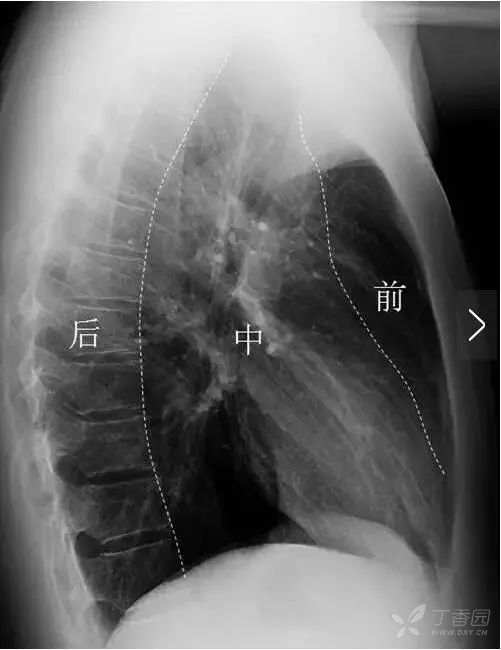

正位胸片上无法看到两肺斜裂。侧位胸片常可见两肺的斜裂(图12)。侧位片也可见水平裂(图12),起自斜裂中点附近,向前水平或稍向下达前胸壁。

图12 三角箭标示两肺斜裂,呈细线状,右肺斜裂起自第4胸椎位置,向前下斜行达横膈前部距前肋膈角约2~3 cm。左肺斜裂起点稍高于右肺,两肺的斜裂在侧位胸片上大致重合。白色箭头标示水平裂,起自斜裂中点附近,向前水平或稍向下达前胸壁 。

通过正侧位胸片结合观察,可以大体判断两肺各叶的位置,能将肺内病变定位到肺叶。各肺叶可进一步分为肺段,肺段间无胸膜作为区分,X线平片不能显示肺段的界限,因此只能通过其解剖位置在胸片上的投影位置进行大致推断。